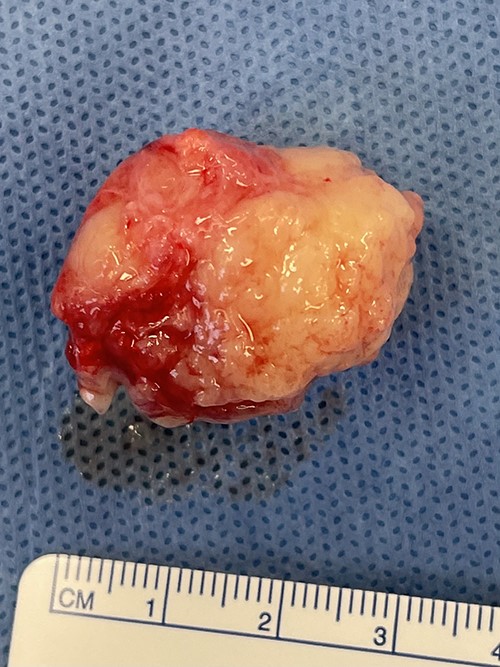

The surgeon performed an intraoral excision of the lesion under general anaesthetic (Fig. 2). It was well circumscribed and confined within the buccal soft tissues. The lesion was removed intact and primary mucosal closure achieved.

Appearance of lesion following buccal sulcus incision and dissection.